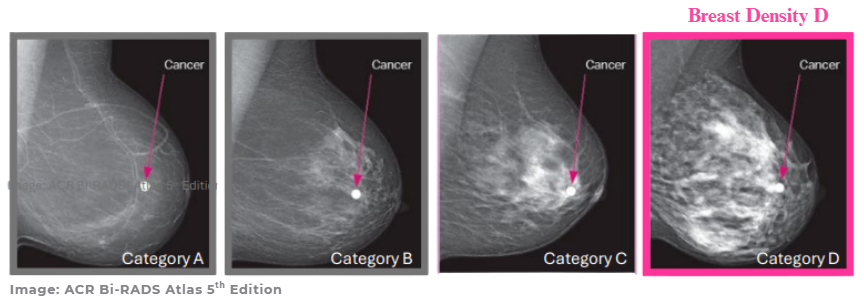

Breast density refers to the amount of glandular and connective tissue compared to fatty tissue seen on a mammogram.1 Dense breast tissue appears white on a mammogram – similar to cancers – making detection of cancers more challenging.2 Research shows that higher breast density not only masks cancers in mammograms but is also an independent risk factor for developing breast cancer.3